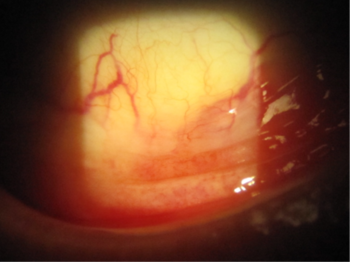

A 69-year-old female patient with unilateral POAG presented complaining of chronic conjunctival injection and irritation. Her condition was stable, based on serial visual field testing and OCT analysis of the optic nerves. Her IOP was 18mmHg with Goldmann applanation tonometry (GAT). Her glaucoma was being treated with latanoprost nocte in the left eye. On this last review she was found to have developed a cataract and was keen to explore her options for reducing or eliminating the drop burden on her ocular surface. Clinical examination revealed significant skin pigmentation and conjunctival injection of the left eye (Figs 1 and 2).

Fig 2. Significant conjunctival injection due to chronic prostaglandin use in the inferior fornix of the left eye

Cataract surgery was performed in combination with implantation of the iStent inject system in the trabecular meshwork. Her postoperative IOP was 14mmHg and the latanoprost drops were ceased in the left eye. Within a month there was a marked improvement in the appearance of her conjunctiva with resolution of the symptoms of irritation. Her forniceal conjunctiva ceased to be injected (Fig 3).

Fig 3. Image of the left conjunctival fornix indicating marked improvement in the appearance of the conjunctiva with resolution of the erythema